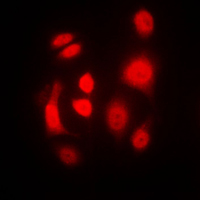

Immunofluorescent analysis of PKR staining in MCF7 cells. Formalin-fixed cells were permeabilized with 0.1% Triton X-100 in TBS for 5-10 minutes and blocked with 3% BSA-PBS for 30 minutes at room temperature. Cells were probed with the primary antibody in 3% BSA-PBS and incubated overnight at 4 °C in a humidified chamber. Cells were washed with PBST and incubated with a DyLight 594-conjugated secondary antibody (red) in PBS at room temperature in the dark.